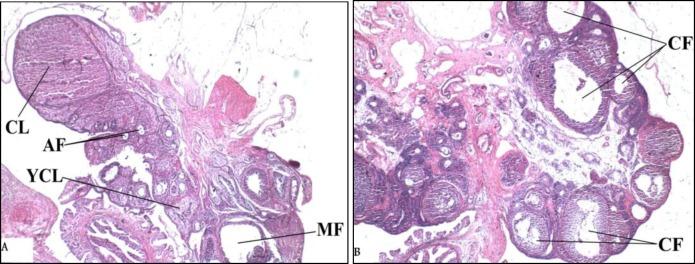

Fifteen female rats (3 wk old) were divided into 3 groups (n=5/each e): Control group, PCO-Control group, and PCO-Resveratrol group. For induction of polycystic ovary phenotype, testosterone enanthate 10 mg/kg was injected for 35 days subcutaneously. Then, resveratrol 10 mg/kg was injected intraperitoneally for 28 days to rats of the PCO-Resveratrol group. Ovarian sections were stained with hematoxylin/eosin. The serum glucose and insulin and the levels of malondialdehyde (MDA) and total antioxidant capacity (TAC) in serum and liver were measured.

Control animals showed normal ovarian morphology and PCO-Control animals exhibited cystic follicles. There were no significant differences in liver TAC between groups. The serum MDA (p=0.034), and homeostatic model assessment insulin resistance (HOMA-IR) (p=0.014) levels in PCO-Control rats were higher than the controls. The liver MDA in PCO-Control rats was more than that of controls (p=0.001). The HOMA-IR (p=0.008) and serum MDA (p=0.006) levels in PCO-Control rats were more than those of PCO-Resveratrol rats (p=0.008). In PCO-Resveratrol group, serum TAC was higher than that of PCO-Control group (p=0.022) and liver MDA was more than controls (p=0.01).